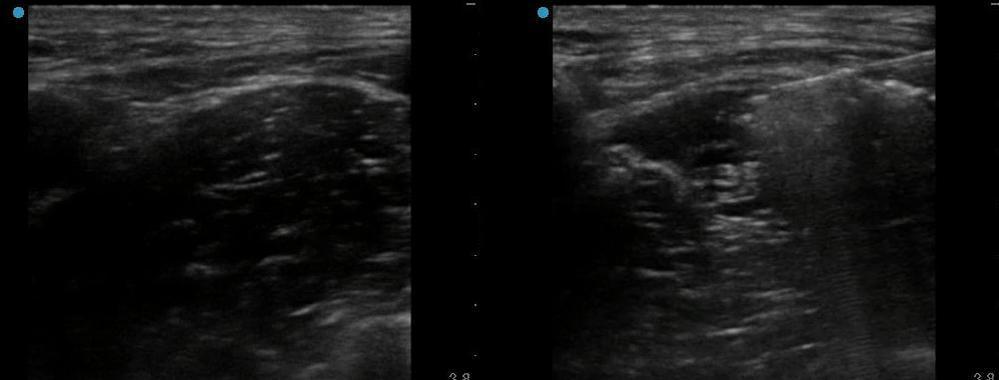

Common errors include placing the probe too low in the leg (after the common femoral artery has bifurcated) or not parallel to the inguinal ligament.

The key for this block is to get fluid underneath the fascia iliaca. I commonly hydrodissect with normal saline to open the space and then add the anesthetic.